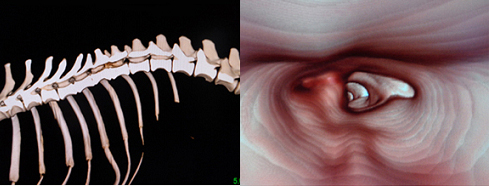

▲椎間板ヘルニアのダックスフンド、膀胱経絡と足三里(ST-36)へのレーザー治療